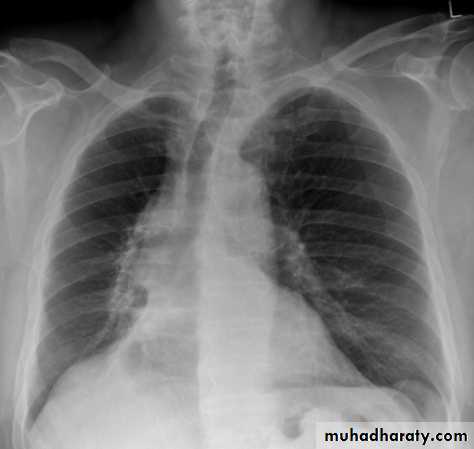

Left lower lobe collapse has distinctive features, and can be readily identified on frontal chest radiographs, provided attention is paid to the normal cardiomediastinal contours. The shadow cast by the heart does however make it harder to see than the right lower lobe collapse

Radiographic features

Left lower lobe collapse

is readily identified in a well penetrated film of a patient with normal sized heart, but can be challenging in the typical patient with collapse, namely unwell patients, with portable (AP) often under-penetrated films, often with concomitant cardiomegaly. Features to be observed include :

triangular opacity in the posteromedial aspect of the left lung

edge of collapsed lung may create a 'double cardiac contour'

left hilum will be depressed

loss of the normal left hemidaphgragmatic outline

loss of the outline of the descending aorta

Non-specific signs indicating left sided atelectasis are usually also be present including:

elevation of the hemidiaphragm

crowding of the left sided ribs

shift of the mediastinum to the left

On lateral projection the left hemidiaphragmatic outline is lost posteriorly and the lower thoracic vertebrae appear denser than normal (they are usually more radiolucent than the upper vertebrae) .